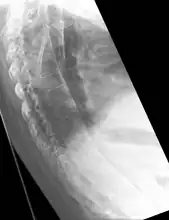

X-rays

The earliest changes demonstrable by plain x–ray shows erosions and sclerosis in sacroiliac joints. Progression of the erosions leads to widening of the joint space and bony sclerosis. X-ray spine can reveal squaring of vertebrae with bony spur formation called syndesmophyte. This causes the bamboo spine appearance. A drawback of X-ray diagnosis is the signs and symptoms of AS have usually been established as long as 7–10 years prior to X-ray-evident changes occurring on a plain film X-ray, which means a delay of as long as 10 years before adequate therapies can be introduced.[19]

Options for earlier diagnosis are tomography and MRI of the sacroiliac joints, but the reliability of these tests is still unclear.